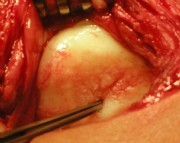

With a tweezer the bone can be reached, the cartilage layer is severely damaged

After cleaning, removal of dead cartilage and replacement of the kneecap back surface with new cartilage